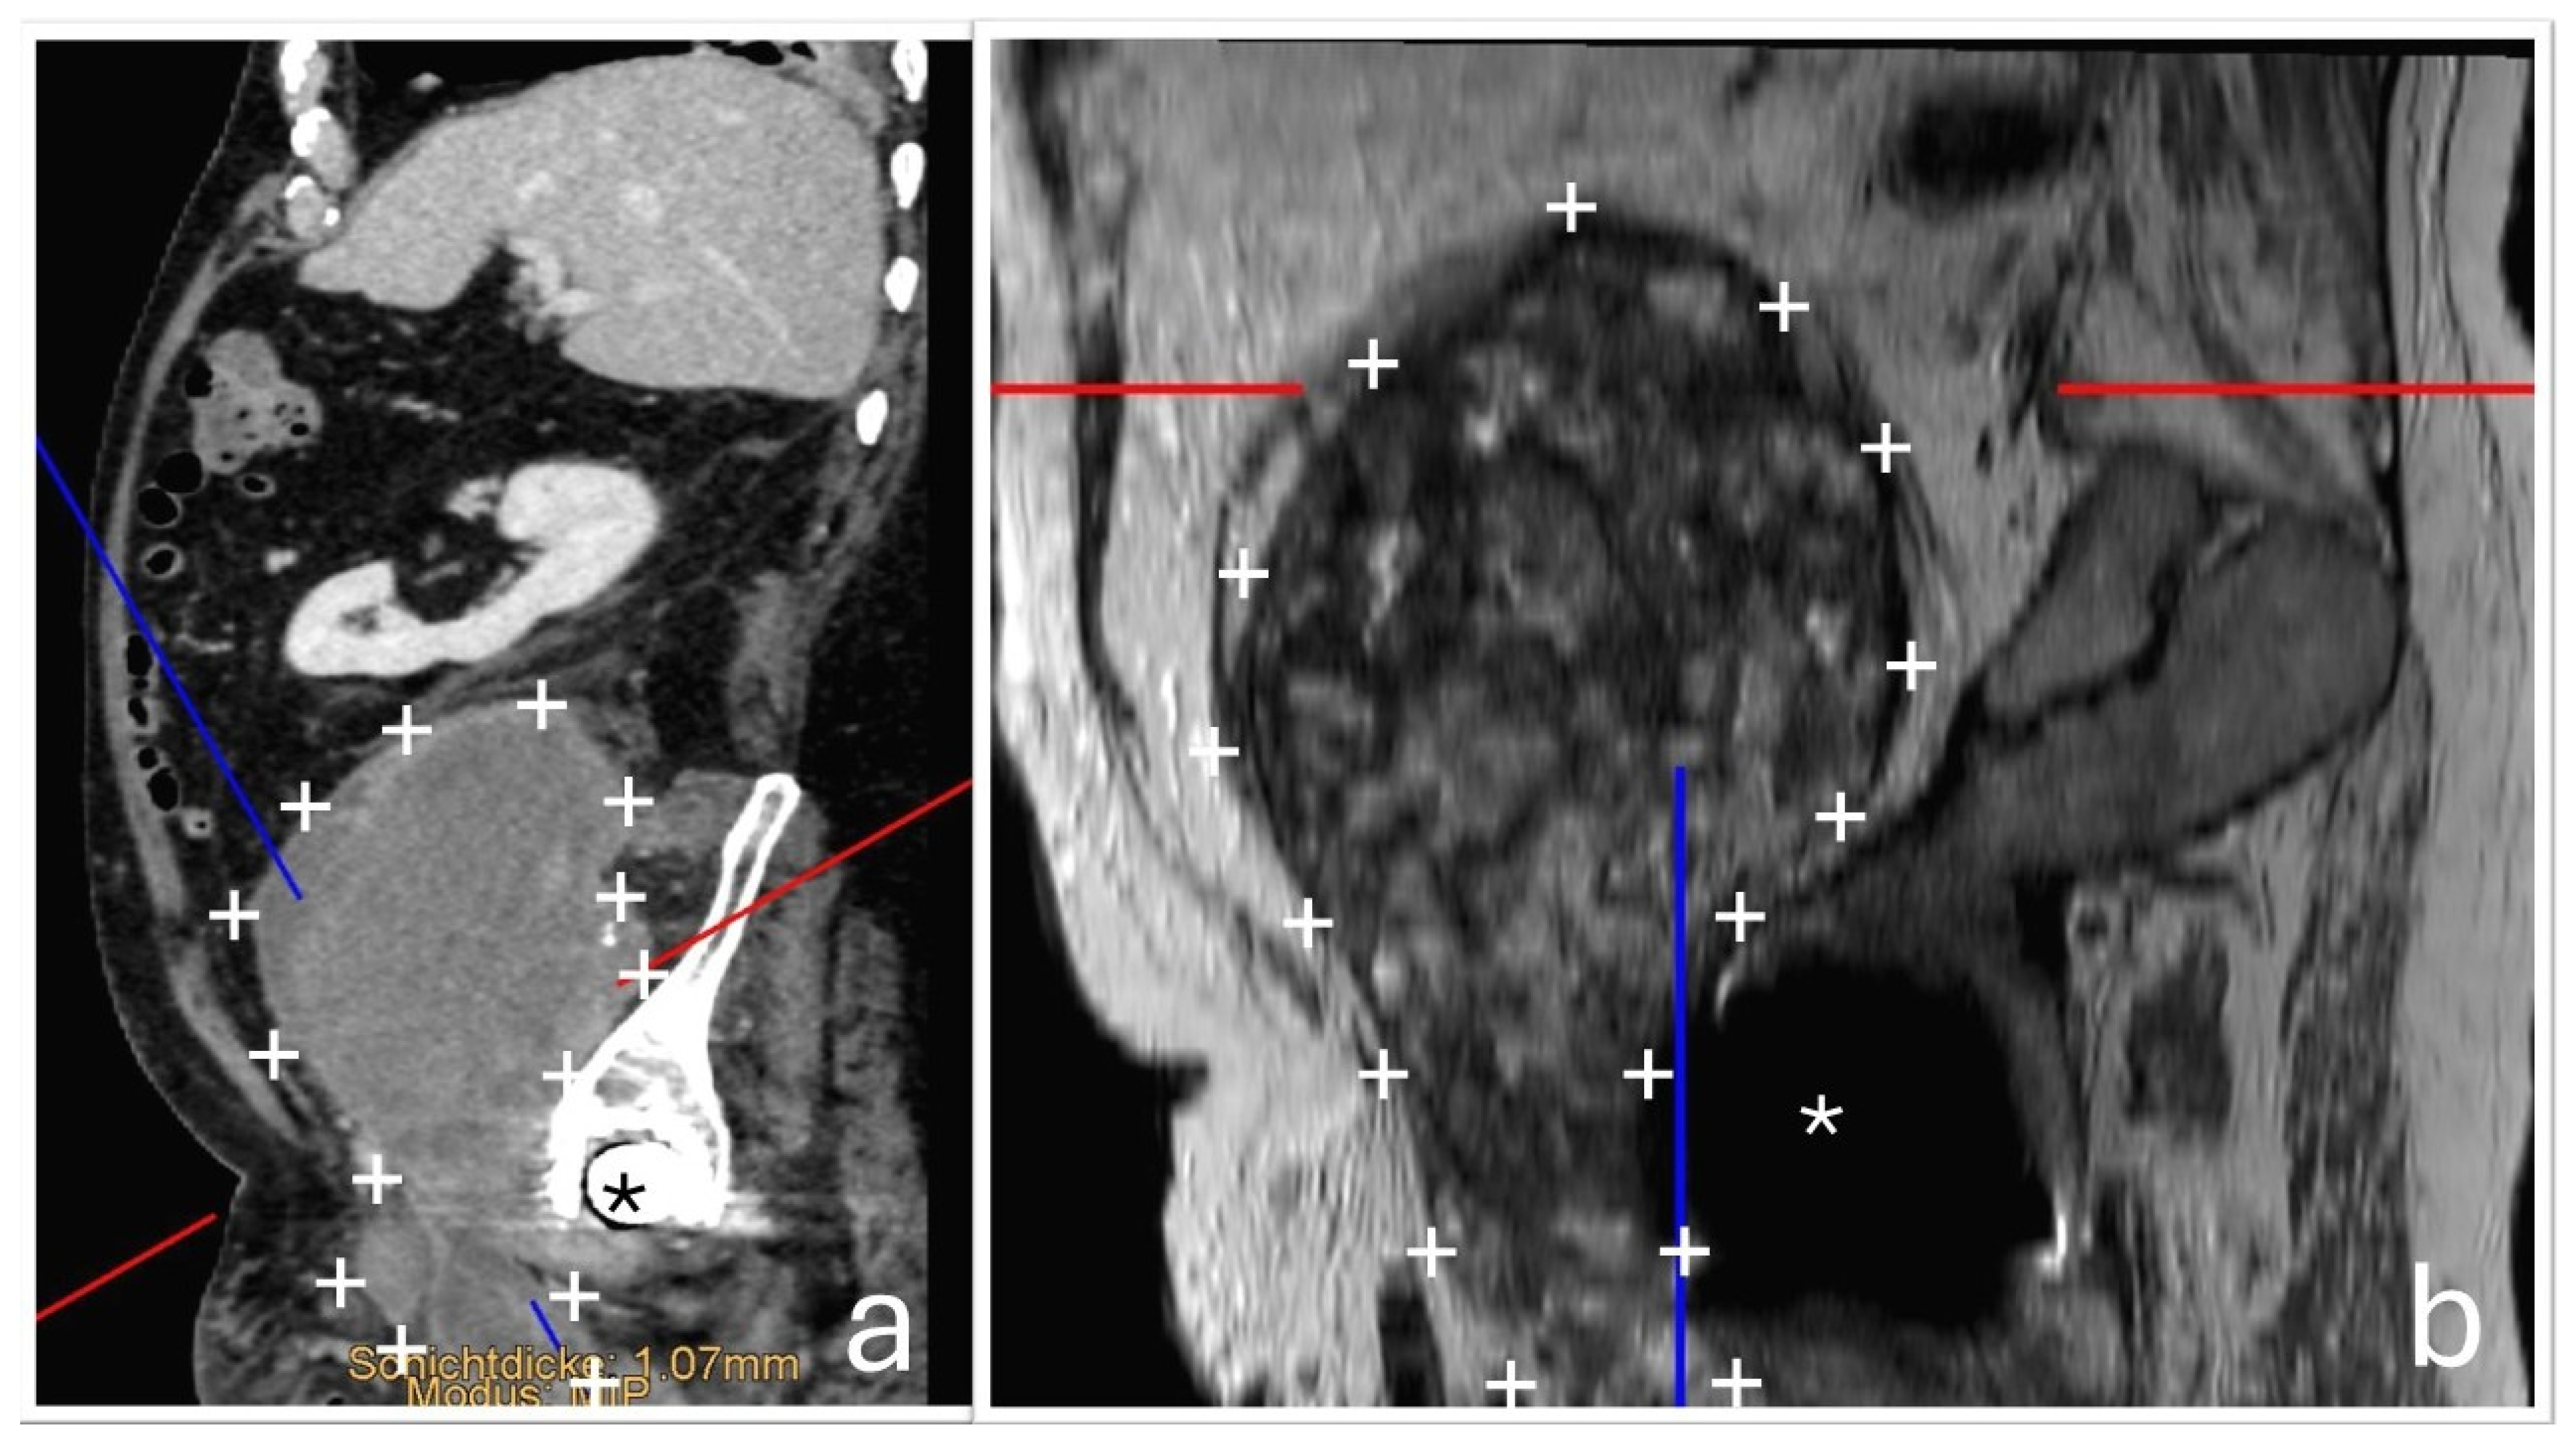

A 75-year-old male patient was transferred to the oncology department of our hospital following the discovery of a large retroperitoneal mass on Computed Tomography (CT) and Magnetic Resonance Imaging (MRI). The lesion, measuring 15 × 13 × 11.5 cm with both cystic and solid components, was adherent to the iliac vessels and suspected to be malignant (Figure 1).

Figure 1. Axial CT (a) and T2-weighted MRI (b) images demonstrate a large, highly heterogeneous retroperitoneal mass in the right pelvis, measuring 15 × 13 × 11.5 cm, with both cystic and solid components and evidence of capsule formation. The lesion displaces adjacent anatomical structures and extends to the infrainguinal portion of the pectineus muscle.